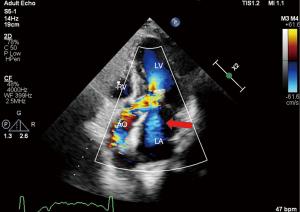

Twelve-lead electrocardiogram showed ST-T segment depression and signs of left ventricular hypertrophy. Transthoracic echocardiography (TTE) showed asymmetric septal hypertrophy with a maximal wall thickness of 16 mm at the LVOT level. Transesophageal echocardiography (TEE) revealed significant SAM of the anterior mitral leaflet (Figure 1, Video 1), causing dynamic LVOT obstruction (Figures 2,3) and severe MR (Figure 2, Video 2). On Valsalva maneuver, the LVOT pressure gradient reached 233 mmHg. Her left atrium was dilated and pulmonary artery systolic pressure was elevated. Reversed systolic wave was observed in the pulmonary vein flow (Figure 4). No abnormal muscle bundles were observed on imaging, including TEE and TTE.

To relieve MR and dynamic obstruction, the team opted for TEER with the MitraClip™ system. Pre-procedural TEE confirmed moderate to severe MR, a mitral valve effective regurgitant orifice area of 0.31 cm2, and a regurgitant volume of 78 mL. The mitral valve area was 3.1 cm2 (planimetrically measured in multiple views), with leaflet lengths of 24 mm (anterior) and 11 mm (posterior). The diastolic mean trans-mitral gradient was 1 mmHg. The regurgitant jet originated from the A2–P2 segment with reversed pulmonary vein flow.